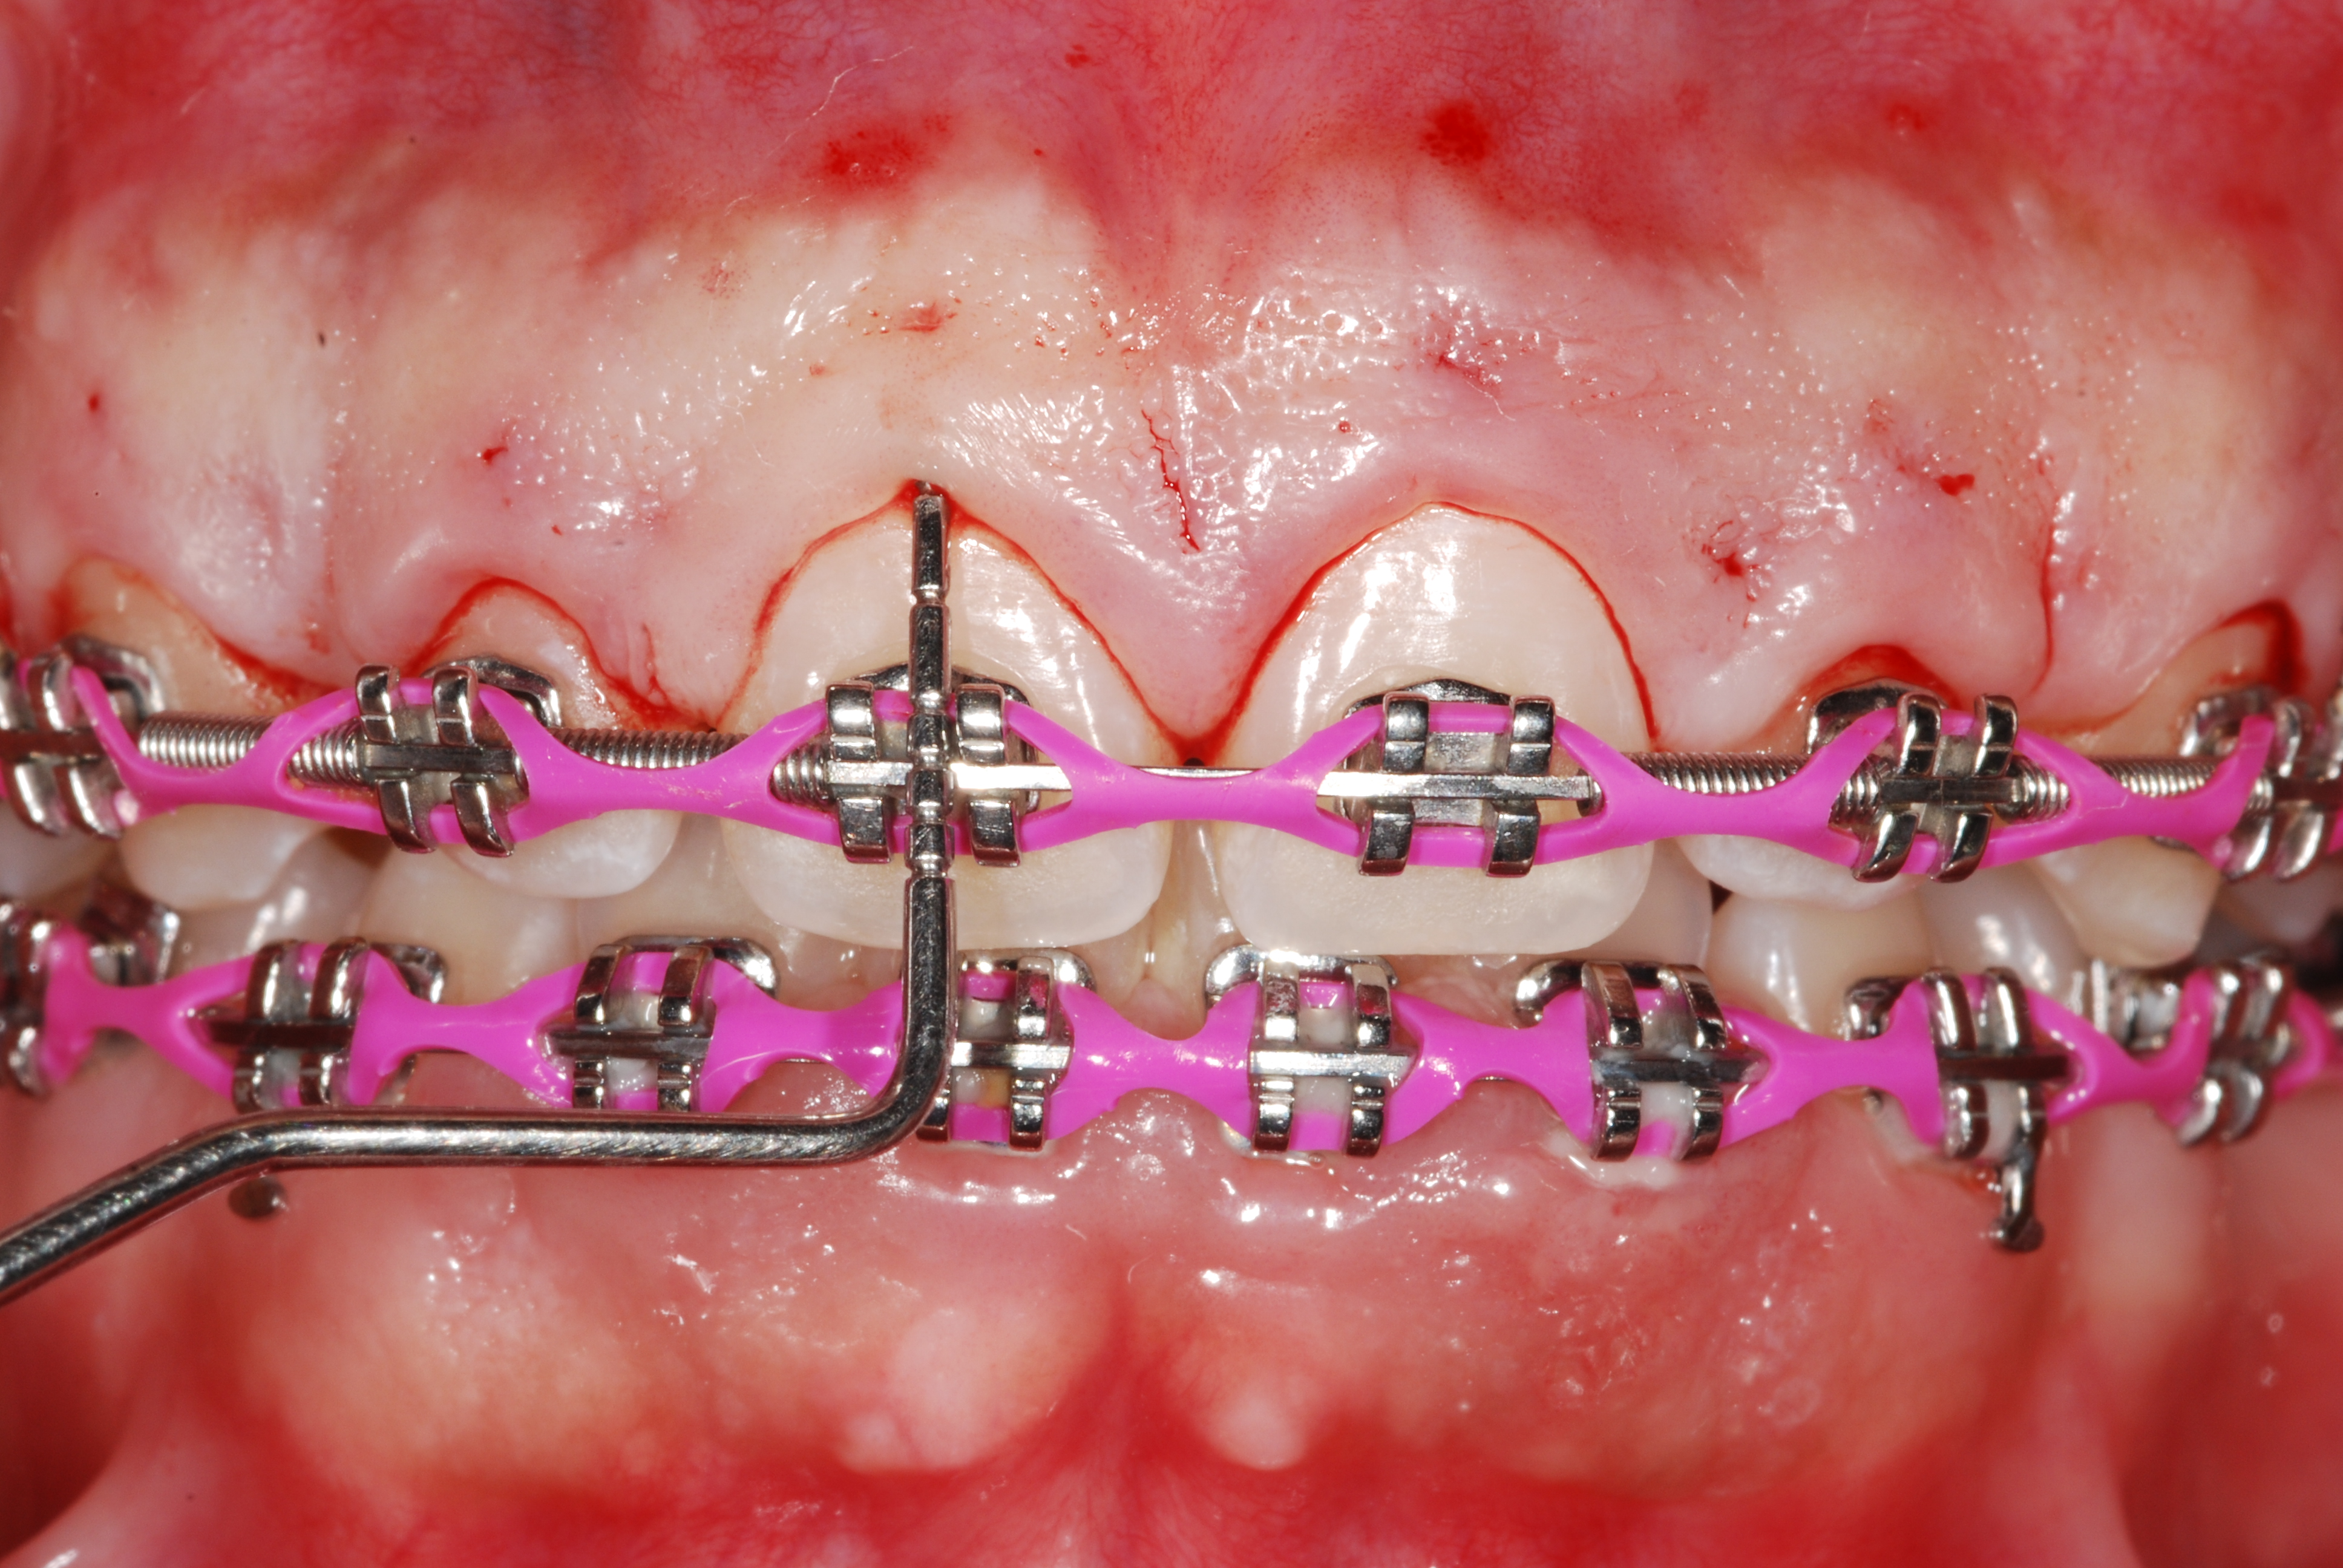

The presence of diastema, between anterior teeth, distorts a pleasing smile by concentrating the observer’s attention on the spaces. The patient’s needs and expectations must be considered in the process of treatment planning to ensure satisfaction with the treatment outcomes. There are many forms of therapy that can be used for diastema closure. A carefully developed diagnosis, which includes a determination of the causal elements and advanced treatment planning, allows the most appropriate treatment to be selected for each case. The aim of this paper is present a multidisciplinary approach as a solution to multiple diastemas in the anterior region using gingival tissue recontouring and direct adhesive restorations, with minimum wear of the dental structure, after the orthodontic intervention discussing the minimal intervention to obtain imperceptive and aesthetic final restoration. Thirty-six months after the treatment was carried out, the final aesthetic was maintained with all dental element details and gingival tissue harmony, without recurrence of periodontal pockets and the preservation of the tooth color and shape.